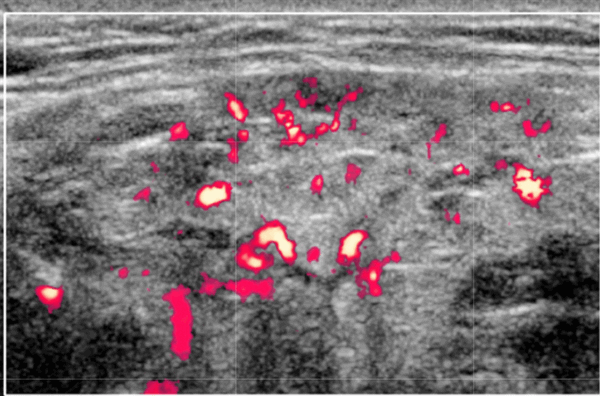

- Повышенная паренхиматозная васкуляризация при СШ на ультразвуковом сканировании с ЦДК

Серошкальное УЗИ. Вовлеченность может казаться асимметричной. Ранние стадии «милиарных» кист (точечные кистозные изменения ≤ 1 мм) могут быть пропущены, однако их легко увидеть на УЗИ на более поздних стадиях. Диффузная железистая гипоэхогенность может быть только признаком раннего синдрома Шегрена, как и неоднородная паренхиматозная эхоструктура. Множественные дискретные гипоэхогенные очаги, разбросанные по слезным и слюнным железам. Солидные очаг представляют собой агрегаты лимфоцитов. Микроцисты возникают из-за деструкции ацинусов или расширения терминального протока из-за сжатия лимфоидными агрегатами. Макроцисты образуются из-за разрушения слюнной ткани. Гиперэхогенные полосы (фиброз) и кальцификаты обычно связанны с хроническим заболеванием. Система балльной оценки УЗИ (основанная на суммировании баллов по эхогенности паренхимы, однородности, наличию гипоэхогенных участков, гиперэхогенных отражений и четкости границ слюнных желез) хорошо коррелирует с результатами биопсии околоушной железы. Лимфоматозное изменение проявляется в виде доминирующего, нечеткого, твердого, гипоэхогенного образования в слюнных железах ± поражение лимфатических узлов.

Цветной допплер. Повышенная паренхиматозная васкуляризация при синдроме Шегрена и коррелирует с тяжестью заболевания

4. УЗИ околоушной железы при синдроме Шегрена:

• На ранних стадиях точечные изменения (кисты менее 1 мм) можно пропустить, но на поздних стадиях нарушения очевидны

• Повышение интенсивности кровотока при допплеровском исследовании

Что покажет УЗИ слюнных желез при болезни Шегрена

- Фиброзные изменения паренхимы

- Уменьшение эхогенности.